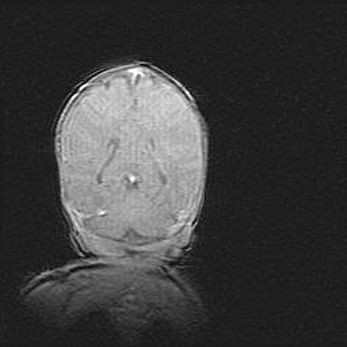

Неполная лизэнцефалия (пахигирия). Открытая гидроцефалия.

Возраст: 17 дней

Вес: 3110 г

Пол: мужской

Окружность головы: 33,5 см

Срок гестации: 35-36 недель

Лизэнцефалия—недоразвитие корковой пластинки и мозговых извилин в результате нарушения миграции нейронов коры. Поверхность мозговых полушарий гладкая. Микроскопически выявляется отсутствие нормальных слоев коры и скопление групп нейронов в подкорковом белом веществе.

Пахигирия—уменьшение числа вторичных извилин. В пораженном полушарии нервные клетки образуют толстый недифференцированный слой с неправильно расположенными нервными волокнами и группами гетеротопных клеток. Нервные клетки незрелые. Белое вещество истончено. При этом нередко аномально развит корково-спинномозговой путь.